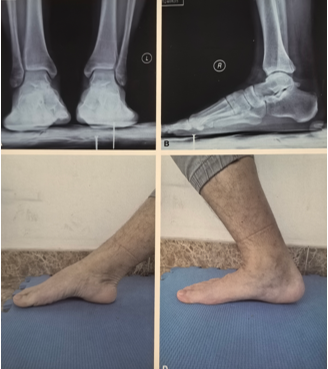

作者选择后外侧入路,先复位腓骨,后踝未予处理,未予三角韧带修补,复位腓骨后检查下胫腓间隙不稳定行下胫腓螺钉固定。术后CT可见下胫腓间隙复位可。作者术中通过复位外踝、下胫腓间隙后透视见内踝间隙匹配可。

术后随访可见患者功能恢复良好。